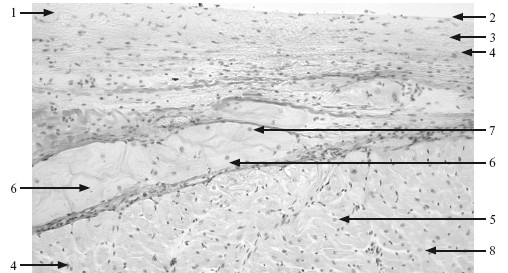

Рис. 11.1. Волокна Пуркинье. ×100.

1 – эндокард; 2 – эндотелий; 3 – субэндотелиальный слой; 4 – мышечно-эластический слой; 5 – миокард; 6 – клетки Пуркинье; 7 – ядро клетки Пуркинье; 8 – сократительные кардиомиоциты.